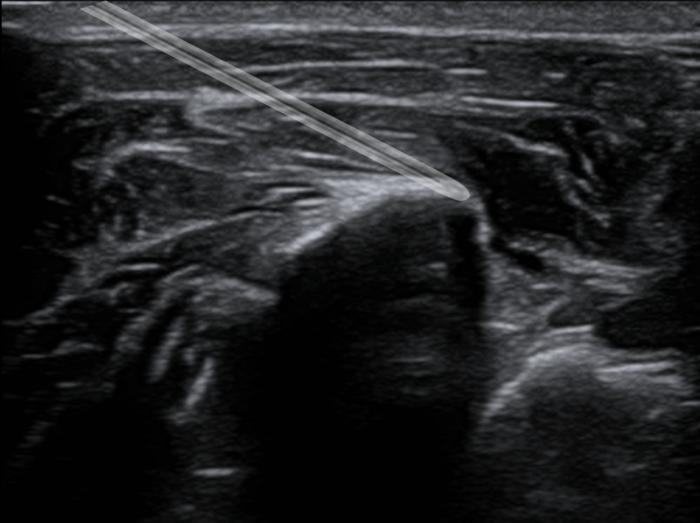

Se prepara el bloqueo a una dosis de 0.3 ml/kg para el bloqueo del GIN y una dosis de 0.5 ml/kg para el bloqueo del cuadrado lumbar caudal. Calculado los bloqueos las dosis en volumen quedarían así:

- Bloqueo GIN: 0.75 ml sitio.

- Bloqueo TONIC: 1.25 ml sitio.

- Volumen total para bloquear = 2 ml.

Sabiendo esto se calcula el bloqueo a una dosis de 2 mg/kg gato de bupivacaína. En México la bupivacaína disponible viene en presentación del 0.5 % por lo que si la llevamos a una dosis de 0.25 % obteniendo así los 2 ml de volumen de bloqueo totales.

Para diluir la bupivacaína del 0.5 % para dejarla al 0.25 % se debe agregar una parte de bupivacaína y una parte de agua estéril o solución salina. Como ejemplo, si al paciente le tocaba 1 ml de bupivacaína al 0.5 % según sus dosis se le agrega 1 ml de salina y así dejamos 2 ml de bupivacaína al 0.25 %.

A esto se sumó dexmedetomidina a una dosis de 1 mcg/kg sitio y triamcinolona a dosis de 0.15 mg/kg sitio. El total en ml de cada medicamento solo se le administra al total de medicamento para el bloqueo. Agregándole así 0.5 ml de dexmedetomidina (100 mcg/ml) y 0.125 ml de triamcinolona (6 mg/ml).

La dosis de volumen total del bloqueo ya con los coadyuvantes fue de 2.61 ml y se realizó al final una aplicación a cada punto un total de 1.7 ml para el TONIC y 0.92 ml al GIN (Figura2-4, Vídeo 2) .